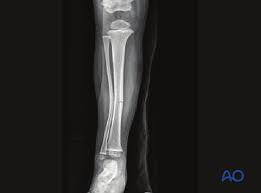

spiral fracture

caused by twisting; break at an angle

stress fracture

caused by overuse injury; tiny fracture lines

bone repair process

1. hematoma formation

2. callus formation

3. callus ossification

4. bone remodeling